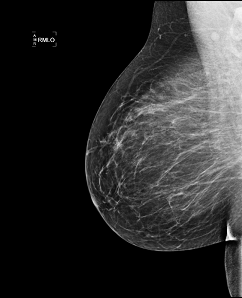

Холецистография, маммография - рентгенография в

условиях искусственного пневмоторакса, пневмоперитонеума и

пневморет-роперитонеума, париетография, фистулография, некоторые

рентгеноэндоско-пические процедуры и другие являются прерогативой

специализированных учреждений онкологического и иного профиля. Самой

Холицистография

Маммография ЭРПХГ

Почечная ангиография Лимфография